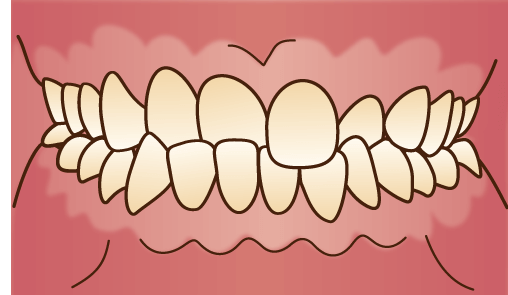

過蓋咬合(かがいこうごう)

正面から見たときに下の歯が見えないほど、上の歯が下の歯に被さっている状態です。深く噛み合った歯が歯茎を傷つけやすく、食べ物も噛みにくいです。状態によっては発音にも影響が出てしまいます。

正面から見たときに下の歯が見えないほど、上の歯が下の歯に被さっている状態です。深く噛み合った歯が歯茎を傷つけやすく、食べ物も噛みにくいです。状態によっては発音にも影響が出てしまいます。